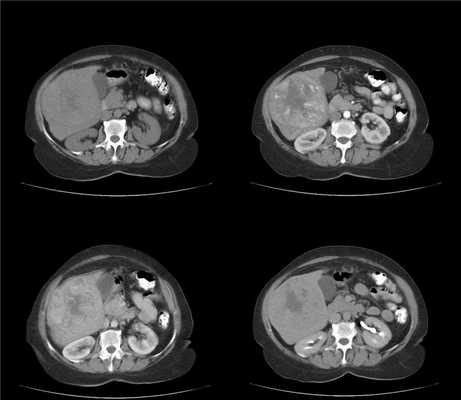

3. КТ признаки регенераторных и диспластических узлов:

• КТ без контрастного усиления:

о Большинство регенераторных узлов достоверно не определяются на КТ или MPT (Т1 ВИ)

о Мелкие узелки изоденсны паренхимы печени, вследствие чего их невозможно обнаружить

о Регенераторные узлы могут выглядеть более плотными по сравнению с окружающей их паренхимой печени:

- Вследствие повышенного содержания железа или гликогена

- Или за счет наличия «гало», обусловленного гиподенсными участками фиброза, окружающими узлы

• КТ с контрастным усилением:

о Регенераторные узлы накапливают контраст несколько хуже по сравнению с тканью печени:

- В результате чего они становятся неразличимыми, «исчезают»

о Диспластические узлы изо- или гиперденсны в артериальную фазу:

- Большинство из них не являются гиперваскулярными

- Избыточная васкуляризация является признаком, подозрительным на ГЦР